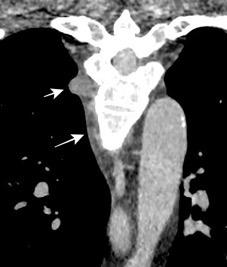

Signos radiológicos TC

Hallifax RJ et al. State-of-the-art: Radiological investigation of pleural disease Respiratory Medicine 2017

Nivel hidroaéreo o burbujas

Forma lenticular o elíptica Ángulos obtusos

> Grasa Extrapleural (60-80%)

Situación no gravitacional (no siempre)

Compresión de estructuras pulmonares

Límite muy bien definido Tabicación

Patrón ecográfico de empiema

Empiema

El derrame paraneumónico se convierte en complicado en 5-10% de los casos

Engrosamiento de la pleura parietal 36/ 59 exudados (61%) 56% de D. paraneumónicos 100% de empiemas Especificidad.. 96%.

Exudado versus trasudado.

Aquino SL, et al. Pleural exudates and transudates: diagnosis with contrast-enhanced CT. Radiology 1994

Signo de la Pleura separada “Split pleural sign”

Capas pleurales de grosor uniforme realzadas por el contraste

Dr. César Pedrosa

No específico de empiema. Indica “exudado”. 68% de pacientes con empiema pleural.

Capas pleurales de grosor uniforme

Realce grasa extrapleural (30%)

> Grasa Extrapleural. (60-80%)

Kraus GJ. Split pleural sign. Radiology 2007